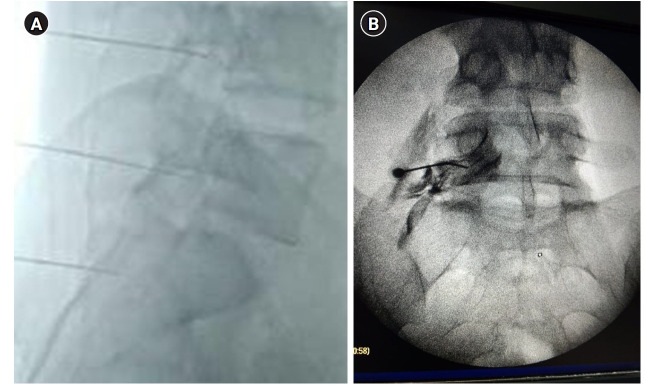

Methods: The current study is a randomized, double blind, clinical trial. The study cohort included population with persistent (> 6 months) back and/or radicular lower limb pain after laminectomy. Group I (HA group) received bupivacaine 0.5% (5 mg), triamcinolone 40 mg, sterile saline (2 ml), and HA (1500 IU) instilled in 1 mL of distilled water. Group II (DEX group) received bupivacaine 0.5% (5 mg), triamcinolone 40 mg (1 ml), DEX (0.5 mcg/kg), and sterile saline (2 ml).